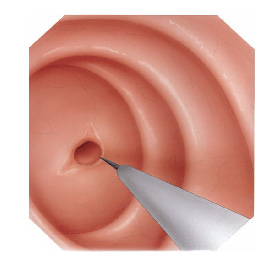

- Dilatadores flexíveis: uma série de sondas graduadas (espessura crescente) chamadas de sondas termoplásticas podem ser usadas. Estes são tubos que passam através do esófago para o estômago. Os tubos utilizados tornam-se progressivamente maior, até que o tamanho desejado seja atingido

- Balões dilatadores: a dilatação do esôfago pode ser feita usando balões durante a endoscopia. A endoscopia flexível permite ao examinador visualizar diretamente a estenose. Um balão é introduzido pelo canal do aparelho até a zona de estreitamento. Ele é então insuflado com água até uma certa pressão, que é pré-ajustada para uma dada circunferência. Quando insuflado, torna-se em forma de salsicha, esticado, e faz com que a estenose se abra.